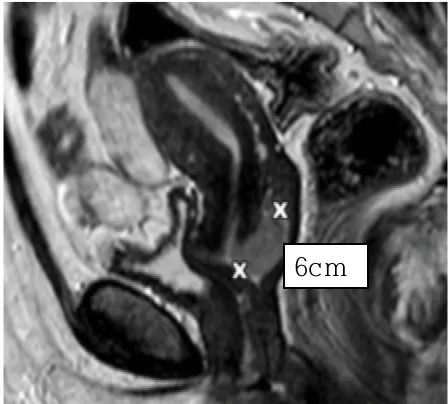

57세 여성이 4개월 전부터 불규칙한 질출혈을 호소하며 병원을 찾았다. 자궁경부에서 쉽게 출혈하는 종괴가 발견되어 조직검사를 시행한 결과, invasive squamous cell carcinoma로 진단되었다. 골반 검사에서 자궁 주변 조직(parametrium) 침범이 의심되었다. MRI 검사 결과 자궁경부 종양의 크기는 기존보다 약간 작았으며, 다른 부위로의 전이는 관찰되지 않았다. 이 환자의 치료 방법은 무엇인가?

• 자궁경부암이 parametrium을 침범했으며 그 이상의 침범은 확인되지 않으므로 stage IIB이다.

• 자궁경부암은 자궁주위조직 침윤 여부를 기준으로 stage IIB 이상부터는 수술이 아니라 concurrent chemoradiation therapy(CCRT)를 시행한다.